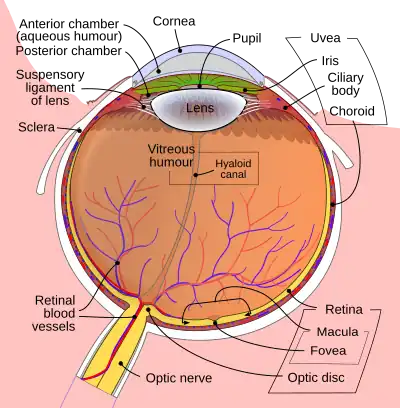

Macular telangiectasia is a condition of the retina, the light-sensing tissue at the back of the eye that causes gradual deterioration of central vision, interfering with tasks such as reading and driving.